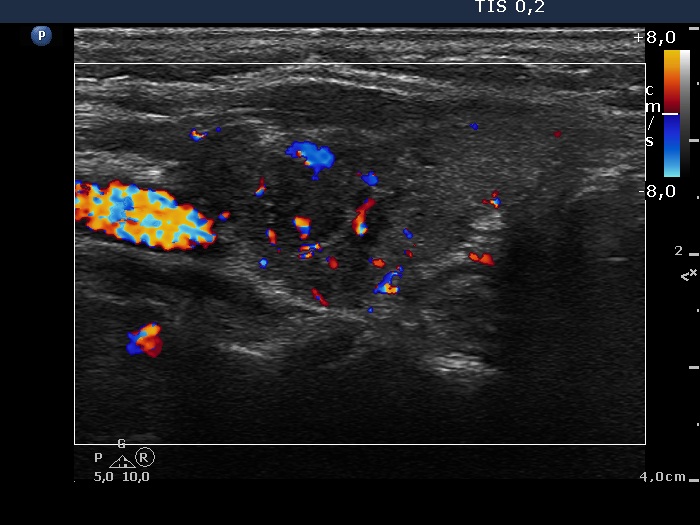

Patient referred for evaluation of thyroid nodule - final diagnosis Hashimoto's thyroiditis - Case 6. (ultrasonographic picture 8)

Left lobe, longitudinal scan, color Doppler mode. The intralesional vascularization is increased.